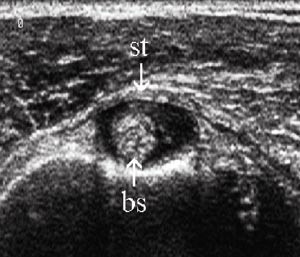

Den lange bicepssenen forløper fra sitt utspring på tuberculum supraglenoidale først intraartikulært svarende til rotatorintervallet. Ned i sulcus intertubercularis følges den av en synovial utposning av leddkapselen (fig 1b). Bursa subacromialis/subdeltoidea ligger i sjiktet mellom rotatorcuffen og musculus deltoideus. Den er normalt atskilt fra glenohumeralleddet.

Vurdering av den lange bicepssenen med ultralyd er mer krevende enn vurderingen av rotatorcuffen. Dette skyldes stor interindividuell variabilitet og hyppige artefakter. Sammenlikning og kontroll av funnene med den kontralaterale siden er derfor påkrevd (8). Typiske funn ved tenosynovitt er enten hyper- eller hypotrofi av senen sammenliknet med motsatt side, redusert ekkogenisitet, ekkofattig halo rundt senen og hvelving av sulcustaket over rotatorcuffnivå (e-fig 11) (3, 9).

Subluksasjon og luksasjon av senen skjer vanligvis i medial retning, og er følge av en skade i det stabiliserende kapsulo-ligamentære apparatet i sulcusområdet. Her inngår musculus supraspinatus og subscapularis som viktige elementer, og bicepsseneluksasjon er derfor ofte kombinert med skade i disse delene av rotatorcuffen (e-fig 12) (1) – (3, 8).

Bicepsseneruptur finnes isolert eller i forbindelse med rotatorcuffruptur. Kriteriene for ruptur er avbrekk av den fibrillære senestrukturen i lengdesnitt (e-fig 13) og manglende senefremstilling i sulcus intertubercularis i tverrsnitt (1, 3).